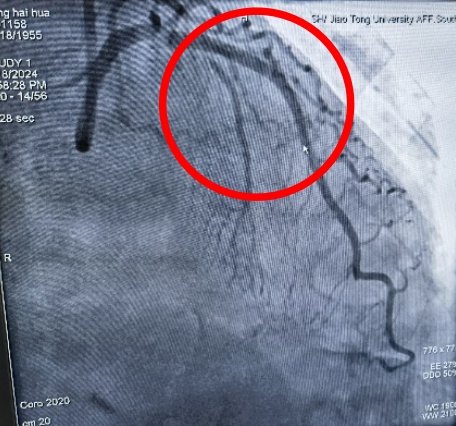

近日,奉贤区中心医院心血管内科开展了奉贤区首例震波球囊术,为复杂冠脉钙化病变再添新武器,进一步开启奉贤区冠脉复杂病变治疗新篇章。 患者张某,69岁,有高血压、糖尿病病史10多年,最近出现不稳定型心绞痛,收住院后择期行冠脉造影检查,造影结果提示:左前降支近段至中远段95%严重狭窄,IVUS(血管内超声)提示360°环形钙化。乔增勇主任团队尝试球囊预扩张,普通球囊+高压球囊反复扩张10余次均不能撼动钙化斑块一丝一毫。乔增勇主任意识到再这样继续扩张下去可能会导致冠脉夹层甚至冠脉穿孔等严重并发症。 高压球囊扩张,呈“狗骨头”效应(箭头处) 在医院的统筹协调下,震波球囊很快到位。乔增勇主任、葛广豪主任医师及杨立国主治医师密切配合,先是利用震波球囊在钙化病变处进行5组脉冲治疗,待钙化的组织被“震碎”后,可见震波球囊完全膨胀,IVUS证实360度“戒指样”钙化环被震开,再次高压球囊扩张后在病变处进行支架植入,术后IVUS进一步证实左前降支架膨胀贴壁好,恢复完全通畅状态,患者病灶得到解除。 术前(前降支95%弥漫性狭窄) 术后狭窄消失 震波球囊技术 震波球囊技术又称血管内冲击波碎石术,是利用设备将电能传递到发射器上,通过发射器产生声波压力波,将球囊内液体汽化,借助气化的液体对血管内膜、中膜的钙化组织进行隔空“敲裂”。 优点: 1.针对性强,只针对钙化组织,对正常血管组织无影响; 2.冲击波治疗后可增加血管顺应性,让血管“恢复年轻态”; 3.有些钙化病变需要震波球囊联合旋磨及切割球囊等“组合拳”方能解决。 奉贤区中心医院心血管内科针对复杂冠脉钙化病变,根据病变特点已成功开展旋磨术,切割球囊及棘突球囊等技术。目前再添新武器“震波球囊技术”,为奉贤区复杂冠脉病变治疗插上新的翅膀,让区内复杂冠脉病变患者不出奉贤即可享受市区三甲医院同质化优质医疗服务。